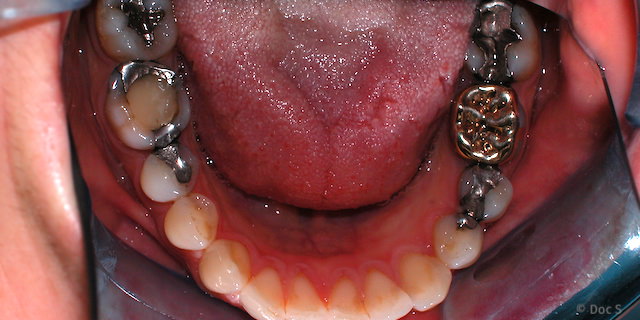

Wenn verschiedene Metalle im Mund vorhanden sind, kommt es zu einem Stromfluss zwischen diesen (sog. "Mund-Batterie"), der u.a. zu Geschmacks-Störungen führen kann.

Verschiedene Metalle im Mund: Goldkrone neben Amalgam-Füllungen